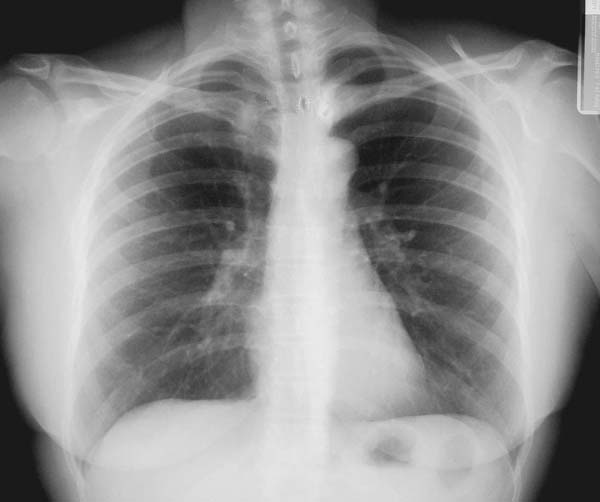

Busque en la placa que sigue todos los indicadores de calidad recién vistos y anote y dibuje las diferencias que usted encuentra y su probable explicación. Una vez anotada su opinión, cotéjela con el comentario que encontrará en la página que sigue. Si hay discrepancias, repita el análisis.

El extremo de la clavícula izquierda está más cerca de la apófisis espinosa que el de la clavícula derecha. Esto indica que el tronco está rotado, con el hombro izquierdo hacia adelante ( oblicua anterior izquierda). Como se ilustra en el esquema adjunto, con este giro la apófisis espinosa se desvía hacia la izquierda de la línes media, mientras que el extremo de la clavícula izquierda se acerca a la línea media. Los hilos pulmonares, al acercarse ambos a la línea media, se confunden parcialmente con el corazón.